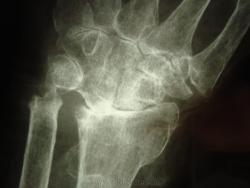

женщина,1930 г.р. , в наравлении -деформирующий артроз? В анализах повышено СОЭ, СРБ, ревмат. фактор.

Рентгенологически выделяют 4 стадии ревматоидного артрита: I стадия (начальная) — только околосуставной остеопороз; II стадия — остеопороз + сужение суставной щели; III стадия — остеопороз + сужение суставной щели + эрозии костей; IV стадия—сочетание признаков III стадии и анкилоза сустава. Раньше всего рентгенологические изменения при ревматоидном артрите появляются в суставах кистей и плюс-нефаланговых суставах.

Ревматологи с областной больницы ставят DS: Ревматоидный  артрит, акт. II. R-стадия III. НФС III. Вторичный ДОА III ст. Анемия хронических заболеваний.